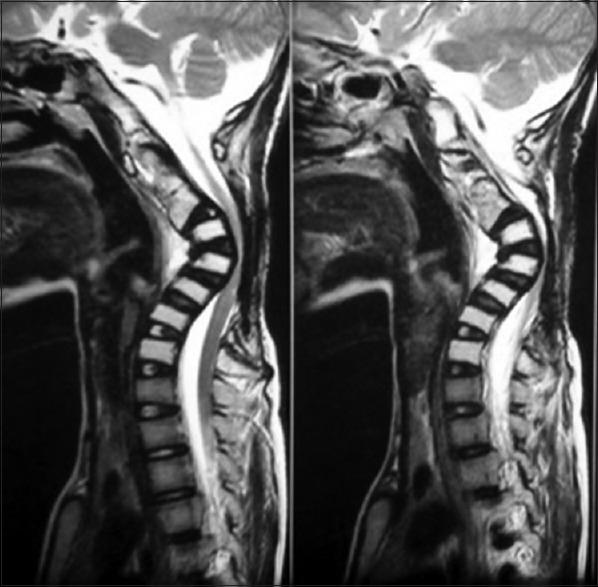

A 14-year-old boy presented with gradually worsening spastic quadriparesis and cervical kyphotic deformity as a consequence of laminectomy for tumor debulking and chemoradiotherapy done 2 years prior for cervical primitive neuroectodermal tumor. Problems to be addressed particularly to the case were a rigid kyphosis of 102.7°, poor soft-tissue coverage, internal gibbus compressing cord, perched facets, and superficial location of cord. The surgery was staged, in that the first anterior release was done with gradually increasing traction to correct the kyphosis progressively. Posterior instrumentation was done in the second stage. Finally, anterior reconstruction with tricortical iliac bone grafting was done. The patient regained full power with complete union at the end of 18 months. Irradiation of tumor along with laminectomy results in loss of posterior tension band which results in progressive kyphotic deformity in children. A staged plan of surgical interventions can help in postoperative correction of deformity with circumferential union and prevention of recurrence. This article describes successful treatment of a patient with postlaminectomy cervical kyphosis with 77° of correction achieved postoperatively and also highlights the importance of anterior and posterior reconstructions to achieve a stable vertebral column.

一名14岁男孩因两年前为治疗颈椎原始神经外胚层肿瘤而进行的肿瘤减瘤椎板切除术和放化疗,出现逐渐加重的痉挛性四肢瘫和颈椎后凸畸形。该病例需要特别解决的问题包括102.7°的僵硬后凸、软组织覆盖差、内部驼背压迫脊髓、关节突高位以及脊髓位置表浅。手术分阶段进行,首先进行前路松解,逐渐增加牵引以逐步矫正后凸。第二阶段进行后路内固定。最后,进行三皮质髂骨移植的前路重建。患者在18个月结束时恢复了全部肌力,实现了完全愈合。肿瘤放疗联合椎板切除术会导致后张力带丧失,从而导致儿童出现进行性后凸畸形。分阶段的手术干预计划有助于术后通过环形愈合矫正畸形并预防复发。本文描述了一名椎板切除术后颈椎后凸患者的成功治疗,术后实现了77°的矫正,同时强调了前后路重建对于实现稳定脊柱的重要性。